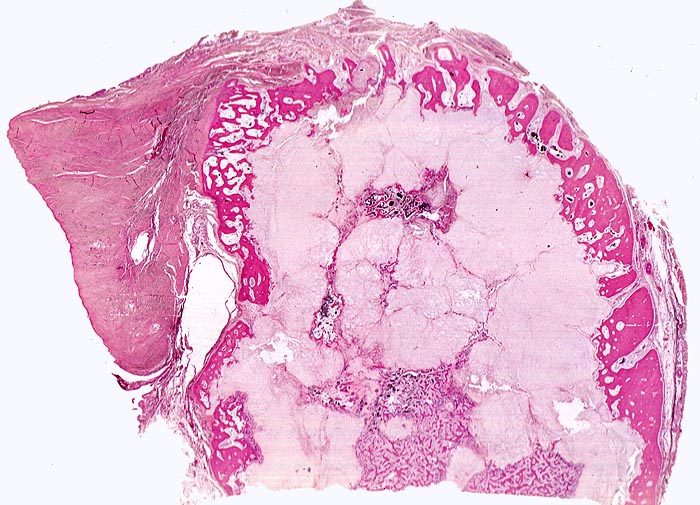

PathoPic ID 4518 - Chondrosarkom

Chondrosarkom

maligner Tumor

Knochen, Rippe

Knochen, Knorpel, Gelenke

In der Übersicht ist ein heller, zellarmer lobulierter Tumor erkennbar.

Zungenförmige Tumorausläufer infiltrieren die angrenzende Kortikalis.

Umschriebene Schmerzen im Bereich des Rippen-Thorax seit über einem Jahr.